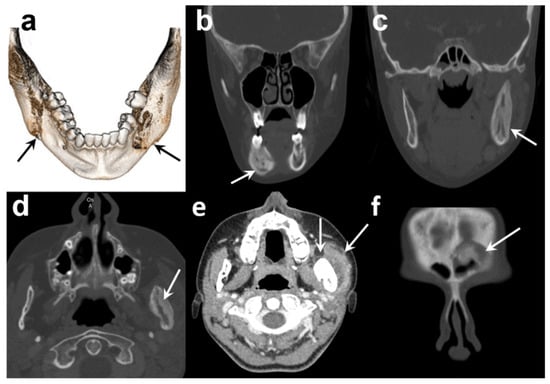

A new CT scan showed that both sides of the mandible were affected, including the right corpus and left ascending ramus, leading to an expansive deformity of the bone. No sequestration was found. Another affected area was detected in the right frontal bone (Figure 2). A bone SPECT (single photon emission computed tomography) registered with this CT scan confirmed the location and areas of metabolic activity corresponding to areas of mandibular and frontal osteosclerosis and osteolysis. No other bone lesions were identified (Figure 3).

Figure 2. Diagnostic CT scan of the patient: (a) 3D reconstruction of mandible, (b) coronal bone-window section of sclerosis and osteolytic in right corpus of the mandible, (c,d) coronal and axial bone window showing an enlargement of left ascending ramus with osteosclerosis with few areas of osteolysis, (e) axial section in soft tissue window revealing a swelling of the left masseter muscle, (f) coronal bone-window section showing an irregular area of sclerosis involving the edge of the left frontal sinus.